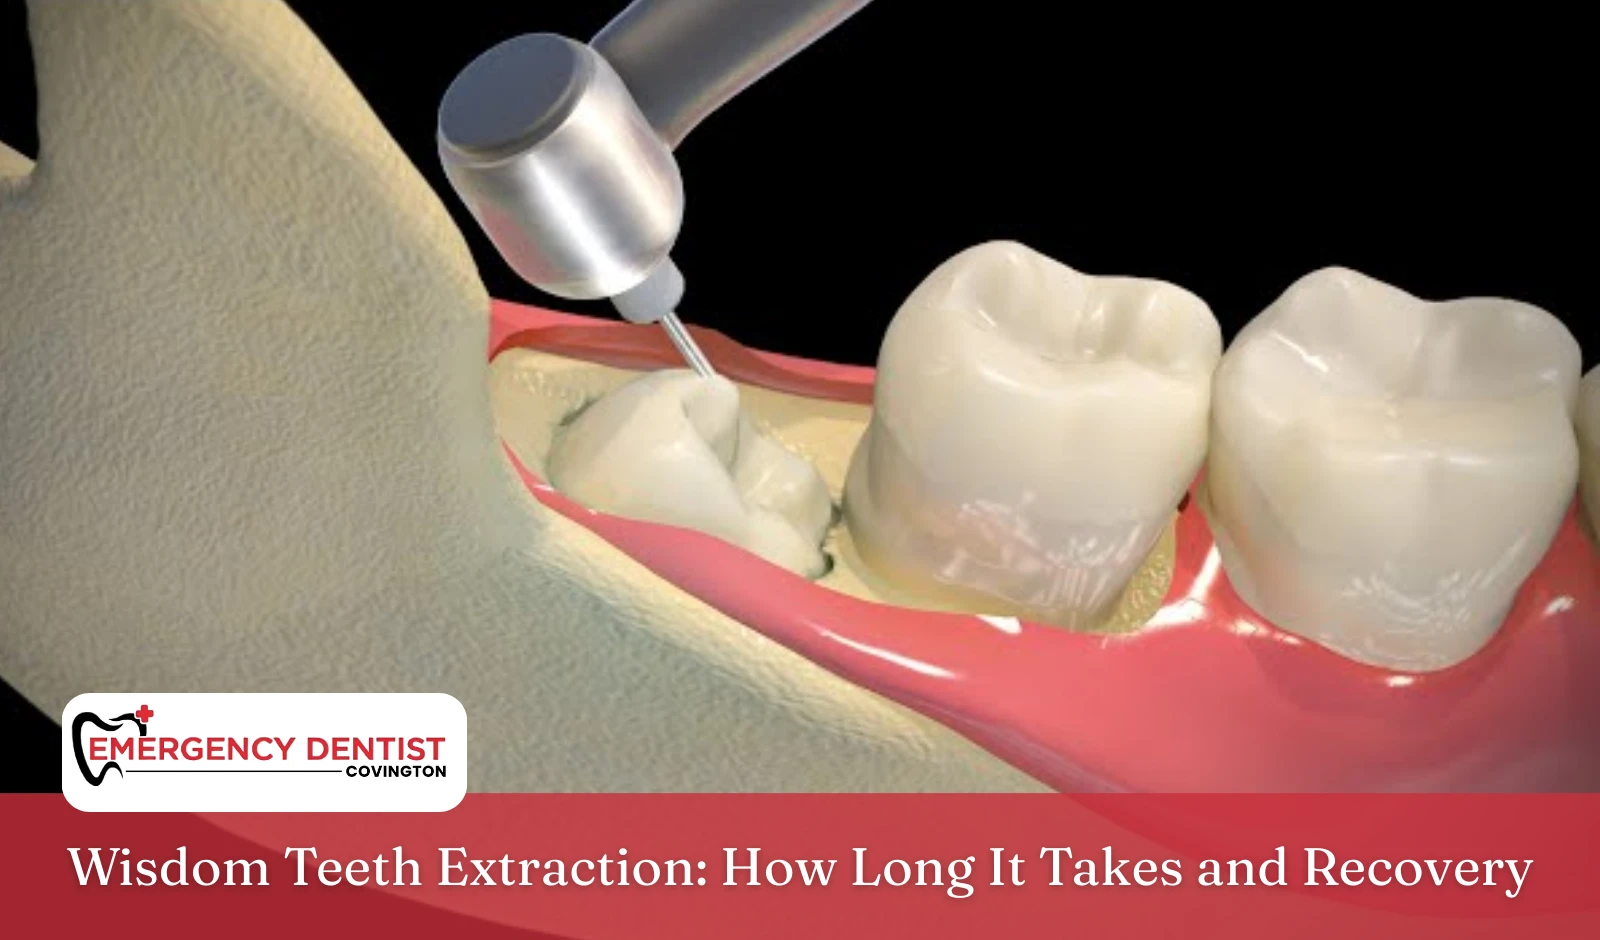

What Is Impacted Wisdom Tooth Removal?

An impacted wisdom tooth is one that cannot fully break through the gums. Some are partly visible, while others remain completely beneath the surface.

Impacted wisdom tooth removal is slightly more involved than a simple teeth extraction. Because the tooth may be beneath gum tissue or partially covered by bone, oral surgery is required. The goal is to carefully remove the tooth while protecting surrounding tissue.

This type of surgical procedural approach is common and safely performed by a trained dentist or oral surgeon.

What Happens During Wisdom Tooth Extraction?

During wisdom tooth removal:

- The area is numbed using local anesthesia

- IV sedation may be offered for added relaxation

- The dentist or oral surgeon gently removes the tooth

- The extraction site is cleaned and prepared for healing

In more complex cases, a small opening is made in the gum tissue to access the tooth. After removal, stitches may be placed to support healing.